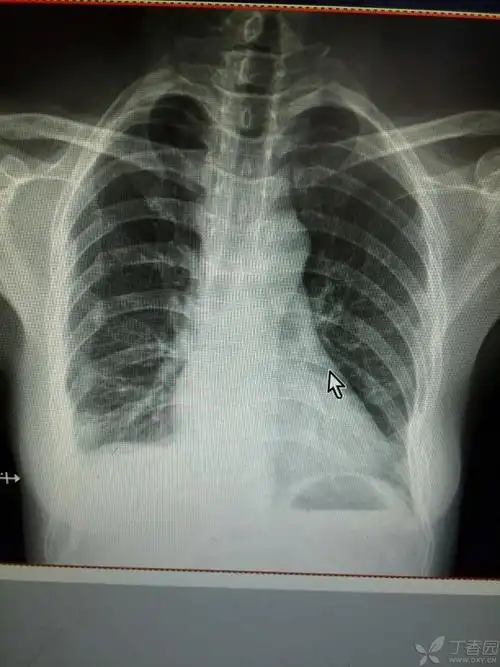

肋骨骨折左侧1-4,右侧5-9,一个半月,之前已经不疼了,这两天稍微活动下